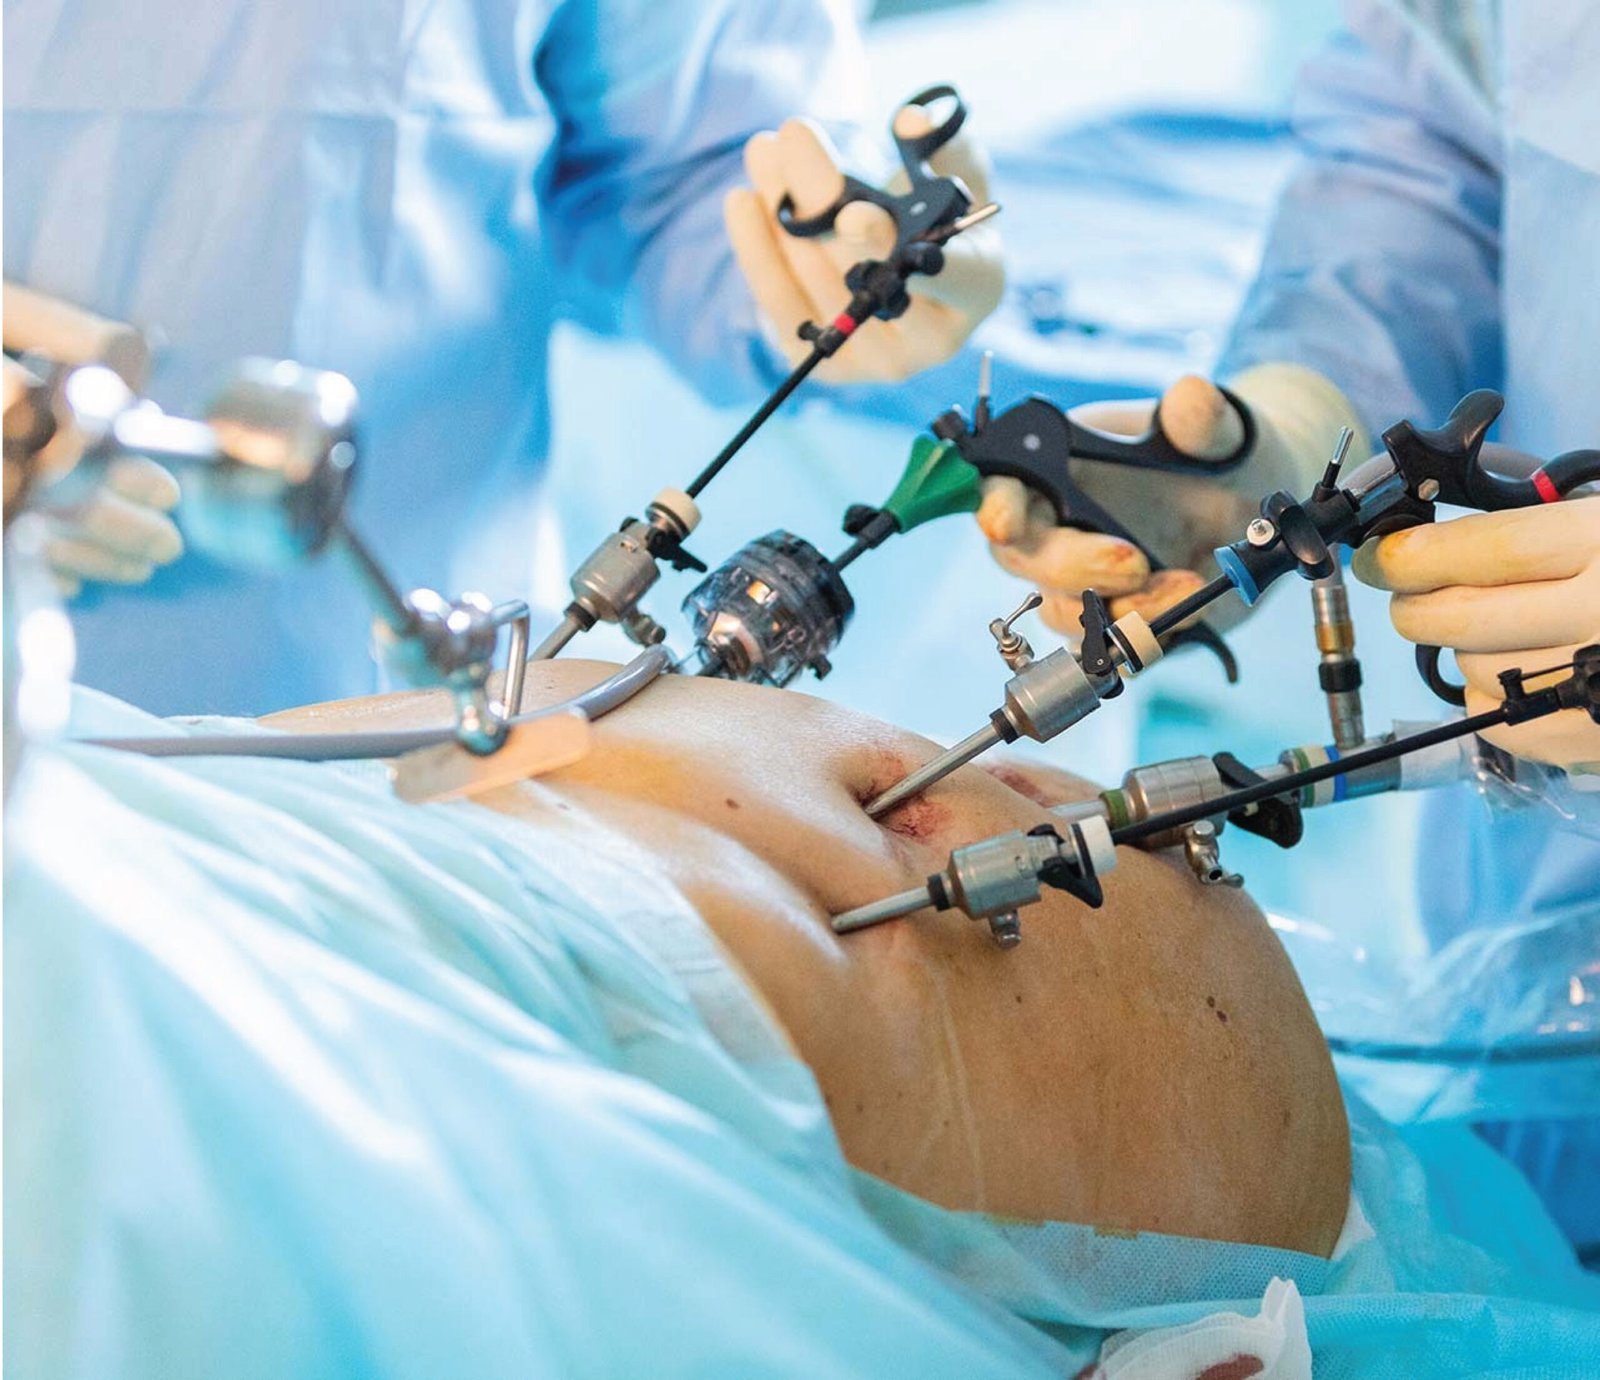

We offer advanced laparoscopic procedures for faster recovery and minimal pain. Expert surgeons handle hernia, liver, gall bladder, and appendix surgeries with precision. Modern equipment ensures safe and effective treatment outcomes. Suitable for patients seeking minimally invasive options.